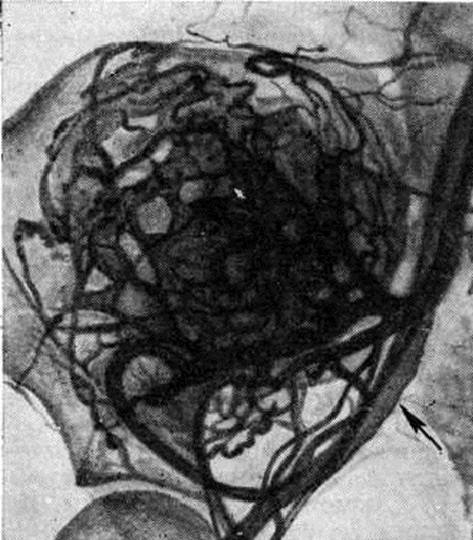

Рис. 2.

Ангиограмма (аортография по Сельдингеру) При кавернозной гемангиоме III поясничного позвонка (указана стрелкой).

При Гемангиома кости никогда не наблюдается сплошного остеолиза или крапчатых склеротических включений, характерных для метастазов опухолей в позвоночник. При компрессионном переломе позвонка с целью дифференциальной диагностики метастаза опухоли и Гемангиома проводят ангиографию. Так, например, в результате ангиографии в теле поясничного позвонка (L3) вместо предполагавшегося метастаза опухоли была обнаружена кавернозная Гемангиома (рисунок 2).